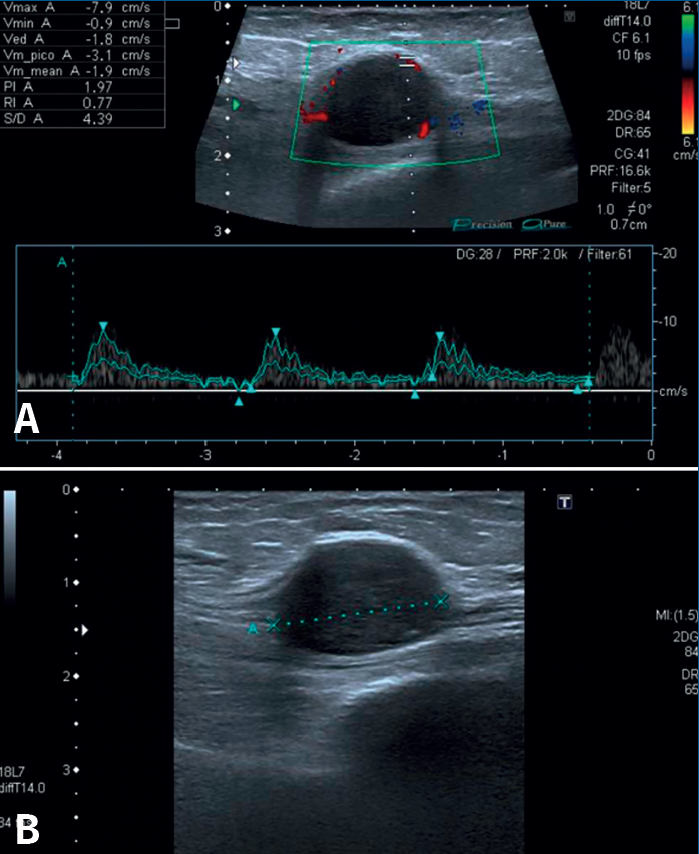

En el estudio histológico que le fue realizado a la tumoración extirpada, el informe describió histológicamente áreas celulares (Antoni A) y áreas hipocelulares (Antoni B), con alto contenido mixoide (Figura 8). Además, no se observaron mitosis ni necrosis, pero sí áreas hialinizadas, pseudoquísticas y con zonas de macrófagos compatibles con alteraciones degenerativas (schwannoma evolucionado).

Los análisis histológicos y patológicos demostrarán que los schwannomas son masas fusiformes de tamaño variable y que tienen verdaderas cápsulas compuestas de epineuro (Figura 7)(8,19). La evaluación microscópica muestra que los schwannomas constan de 2 tejidos distintivos, la región de Antoni A, que es densamente celular y ordenada en haces cortos o fascículos entrelazados (cuerpos de Verocay), y la región de Antoni B, que tiene menos células y áreas desorganizadas con un mayor componente mixoide dispuestas en un estroma suelto como mostramos en las Figuras 8 y 9(9,14,19,21,28). Hao et al.(19) nos informan en su estudio, además, que cuando en la histología nos encontramos zonas de proliferación de células fusiformes concéntricas alrededor de los vasos sanguíneos con haces irregulares junto con áreas de necrosis, anaplasia y mitosis excesiva, debemos pensar en malignidad (neurofibrosarcoma), aspectos que no fueron encontrados en nuestra masa. Con respecto a la inmunohistoquímica, los schwannomas suelen mostrar una expresión fuerte y difusa de la proteína S100(29,30,31). Folpe y Gown han declarado que la inmunotinción de la proteína S100 y vimentina identifica sistemáticamente los schwannomas y que sirve como una importante herramienta de diagnóstico debido a la fuerza de su expresión(9). En el caso de nuestra paciente ambas fueron positivas y se observó abundante colágeno de tipo IV pericelular(32). Además, presentó un Ki-67 < 5%, por lo que el marcador de proliferación celular era de benignidad. Por tanto, la clínica, junto con los estudios de imagen y el estudio anatomopatológico, permitieron objetivamente diagnosticar a nuestra paciente de schwannoma benigno dependiente del NTP.

Figura 8. Microfotografía realizada con tinción de hematoxilina y eosina, donde se muestran áreas Antoni A con tejido fibrilar, intensamente polar y de apariencia alargada, y áreas Antoni B constituidas por regiones microquísticas sueltas, distintas y adyacentes a las regiones de Antoni A.